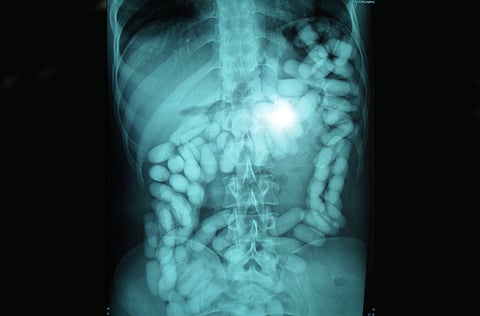

X-ray at Muscat International Airport reveals alleged smuggler had swallowed the drugs

The police did not find anything objectionable in his bags or on his person but he was taken to the ROP hospital in Qurum where an X-ray revealed 134 capsules of narcotics, police said.